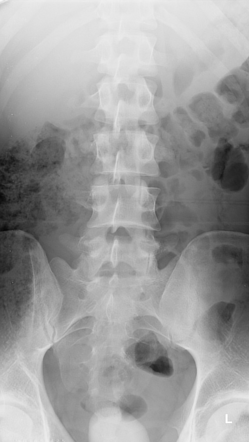

A lumbosacral spine x-ray is an imaging test is performed to view the anatomy of the lower back. It gives a clear picture of the lumbar vertebras (small bones) in the lower part of the spine. It includes the area that connects the spine to the pelvis (lumbar region and the sacrum)

The most common reason, the doctor recommends a lumbosacral spine x-ray is to find the root cause of severe low back pain present in an older person that occurs after an injury and doesn’t go away after 4 to 8 weeks.